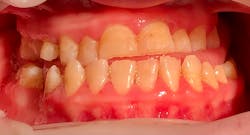

Katie presented with multiple areas of dental decay, heavy plaque buildup, and light to moderate supragingival calculus with little subgingival calculus. There are signs of bruxism with wear and small fractures on her teeth (figures 1 and 2). Katie has a large tongue that often covers her teeth while her mouth is open (figure 3). She has an anterior and posterior crossbite (figure 4) and a retained primary tooth. Katie was cooperative for radiographs, which were taken while working with her verbally and using positive wording and demonstrations. Extra time was taken to allow her to process what was being described and to abate her fears.